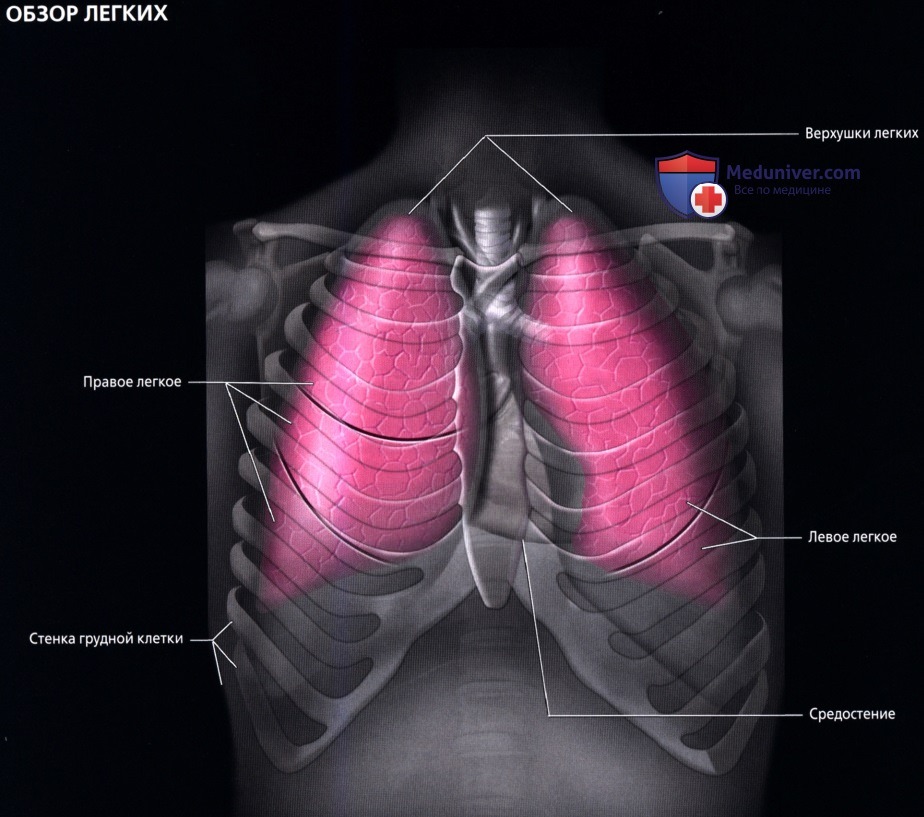

Анатомические изображения сегментов легких различных животных

Раздел: Другие животные